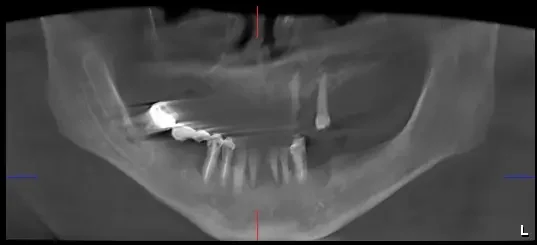

Pacientul a venit la noi cu boala parodontala avansata, care a dus la pierderea dintilor si afectarea structurii osoase. Purta doua proteze mobile instabile, cu care nu reușea sa mănânce.

• Consultul inițial – Am discutat despre dorințele pacientului și am făcut o evaluare completă a sănătății orale.

• Am extras dinții irecuperabili.

• Am efectuat o reabilitare completa prin inserarea a 6 implanturi la maxilar si 6 implanturi la mandibula. In 24 de ore, a primit doua lucrări provizorii fixe, care a asigurat functionalitate si estetica imediata.